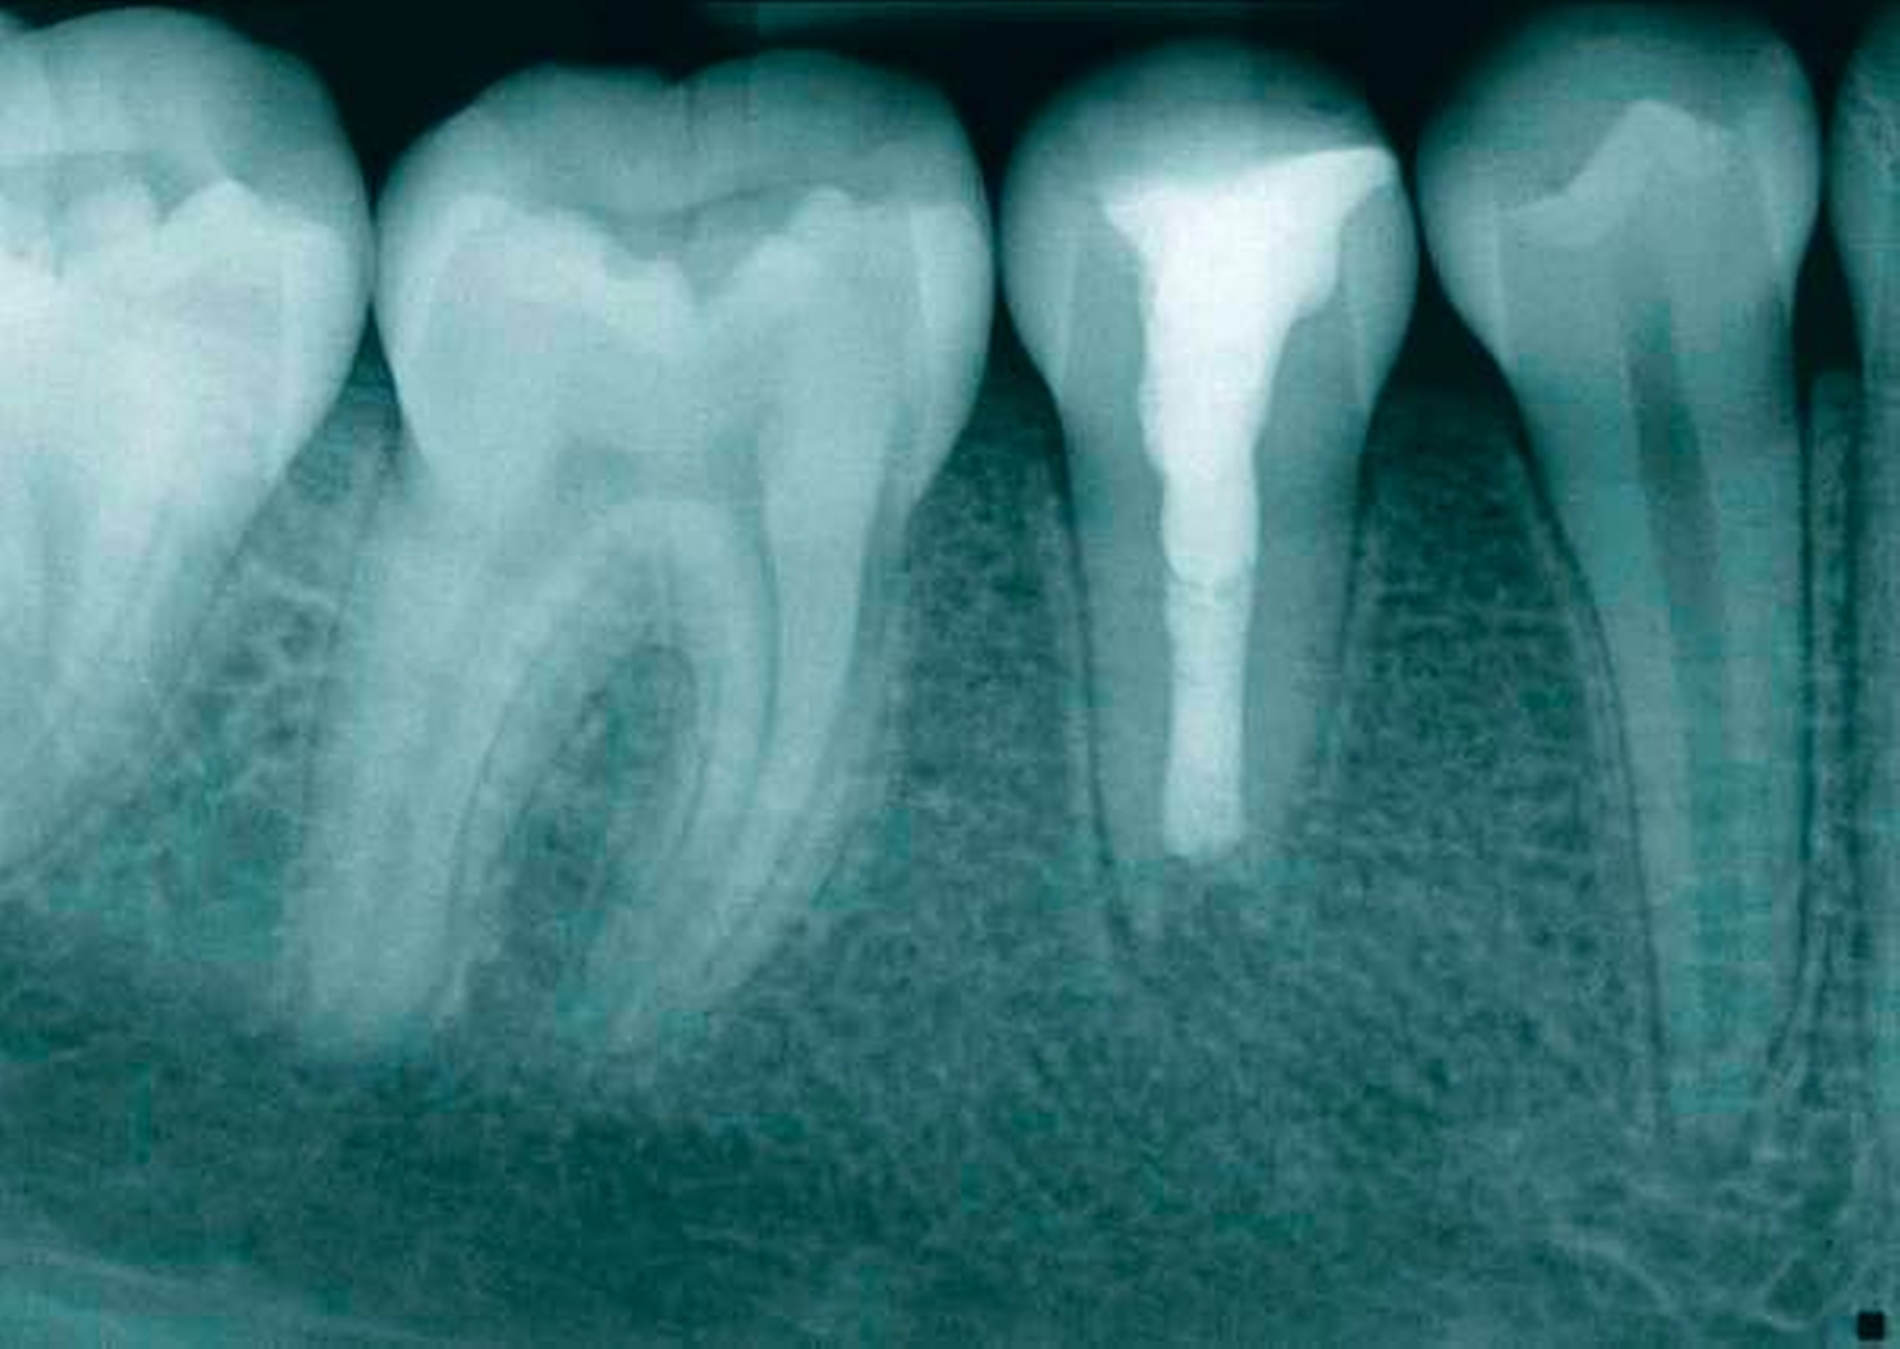

Das Ausgangsröntgenbild (Abbildung 1) der Regio 44–46 zeigte eine apikale Transluzenz im Bereich der Wurzelspitze des Zahnes 45. Der Zahn weist ein nicht abgeschlossenes Wurzelwachstum mit weit offenem Foramen und weitlumigem Wurzelkanal auf. Im Bereich der klinischen Zahnkrone imponiert eine transluzente, kariesdichte Zone, die sich vom mesialen Anteil der Krone bis ins Pulpenkavum erstreckt. Die Fissur des Zahnes scheint stark invaginiert und ist radiologisch nachzuvollziehen.

Klinisch stellte sich der Zahn als nicht perkussionsempfindlich dar und reagierte nicht auf den Kältetest. Es lag keine Schwellung vor, jedoch ein Fistelgang lingual des Zahnes 45 (Abbildung 2) sowie eine leichte Druckdolenz im Vestibulum Regio 45. Eine große Kavitation, wie es das Röntgenbild vermuten lässt, war klinisch nicht festzustellen (Abbildung 2). Die Nachbarzähne reagierten adäquat auf den Kältereiz und waren perkussionsunempfindlich. Die Fissurenversiegelung an Zahn 46 wurde als insuffizient bewertet.

Als Diagnose ergab sich ein avitaler Zahn 45 mit nicht abgeschlossenem Wurzelwachstum und periapikaler Läsion mit einer unterminierenden Karies profunda als Eintrittspforte für die Bakterien ins Wurzelkanalsystem.